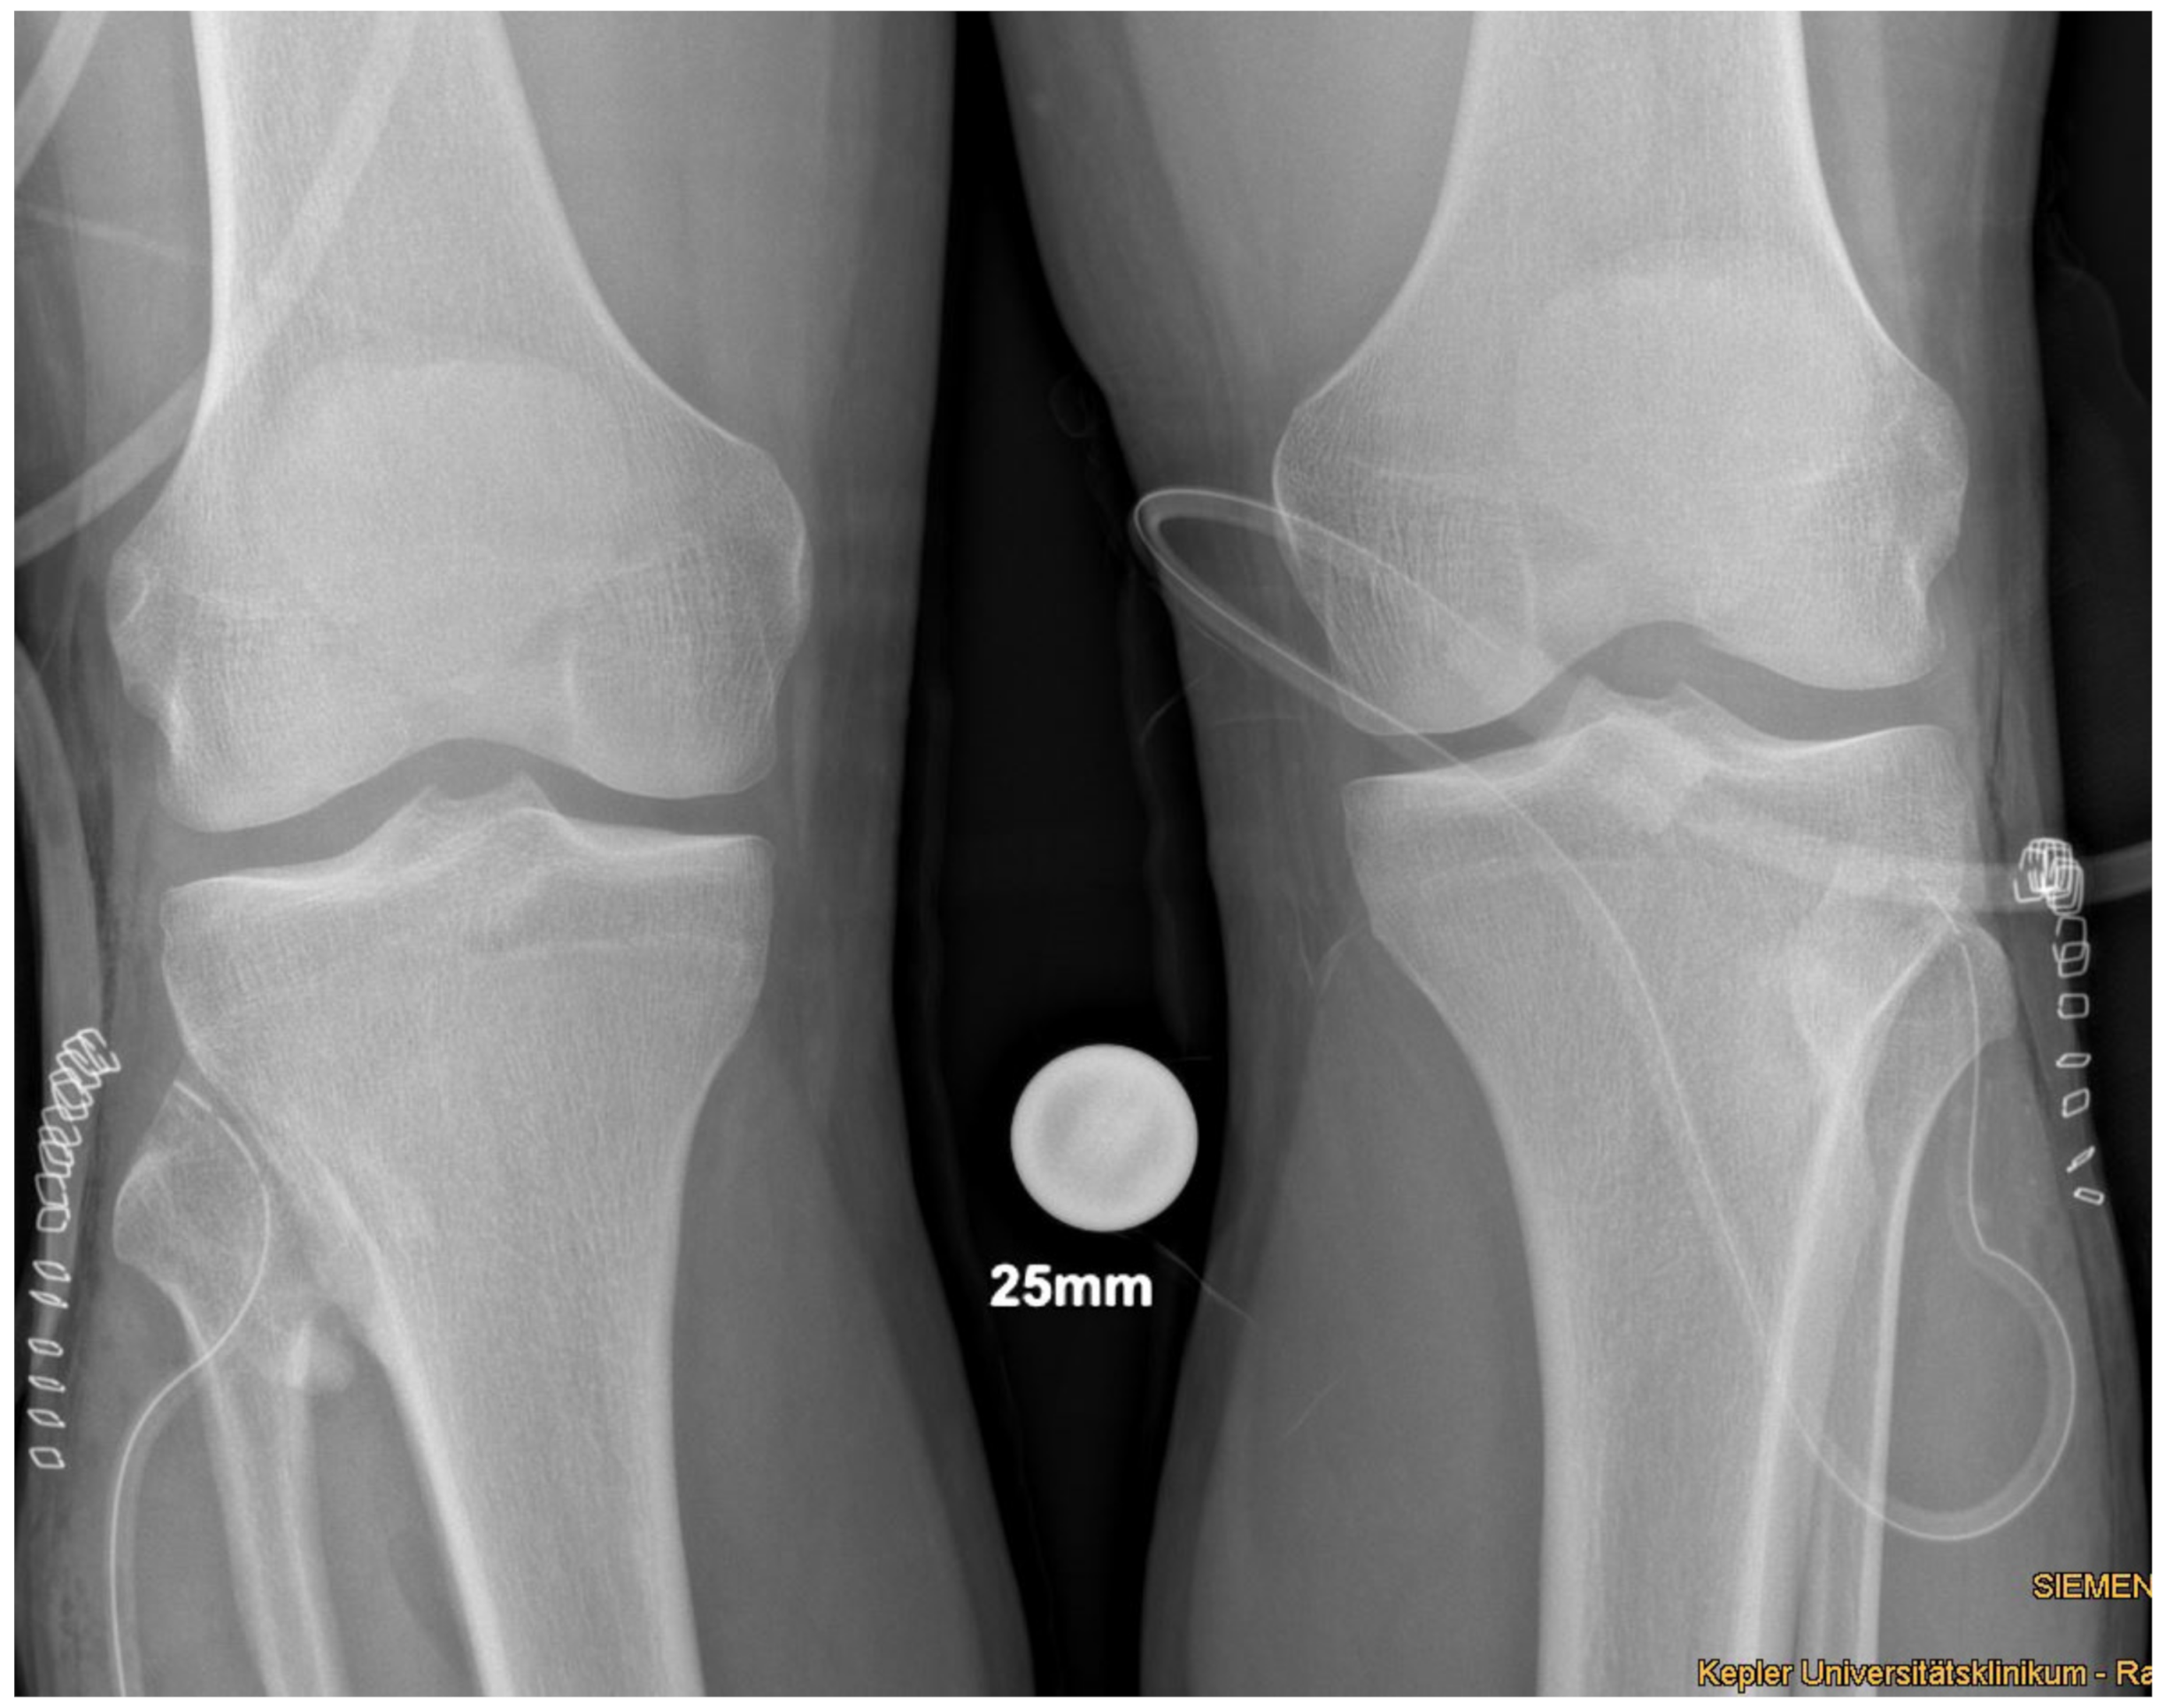

In supine position and under general anesthesia, both lower extremities were washed and draped in sterile cloth. Surgery was started using Esmarch’s-Method on the left side. The approach was direct anterolateral towards the tibiofibular joint, about 4cm in length. Passing the subcutaneous fat tissue, the crural fascia was dissected, and the proximal part of the anterior tibial muscle was pushed medially and retracted with hooks. Then, the synostosis was visible. The surface of the synostosis was primed with a rasp, and a Hohmann hook was placed proximal and distal. Then, the synostosis was excised with a chisel and a Luer pincer. The gap between the tibia and fibula was considered to be broad enough when a distance of 5mm was reached (Figure 4). Then, the situs was flushed with saline, bone wax was stuck to the open fibular and tibial bone to prevent reossification, and stepwise closure of the wound was performed. A drain was used. The procedure was then performed on the right side in the same way. A postoperative biplane X-ray was performed (Figure 5).

Figure 4. Intraoperative situs before (left) and after resection (right) of the synostosis of the left side; top = anterior, bottom = posterior, right = proximal, left = distal.